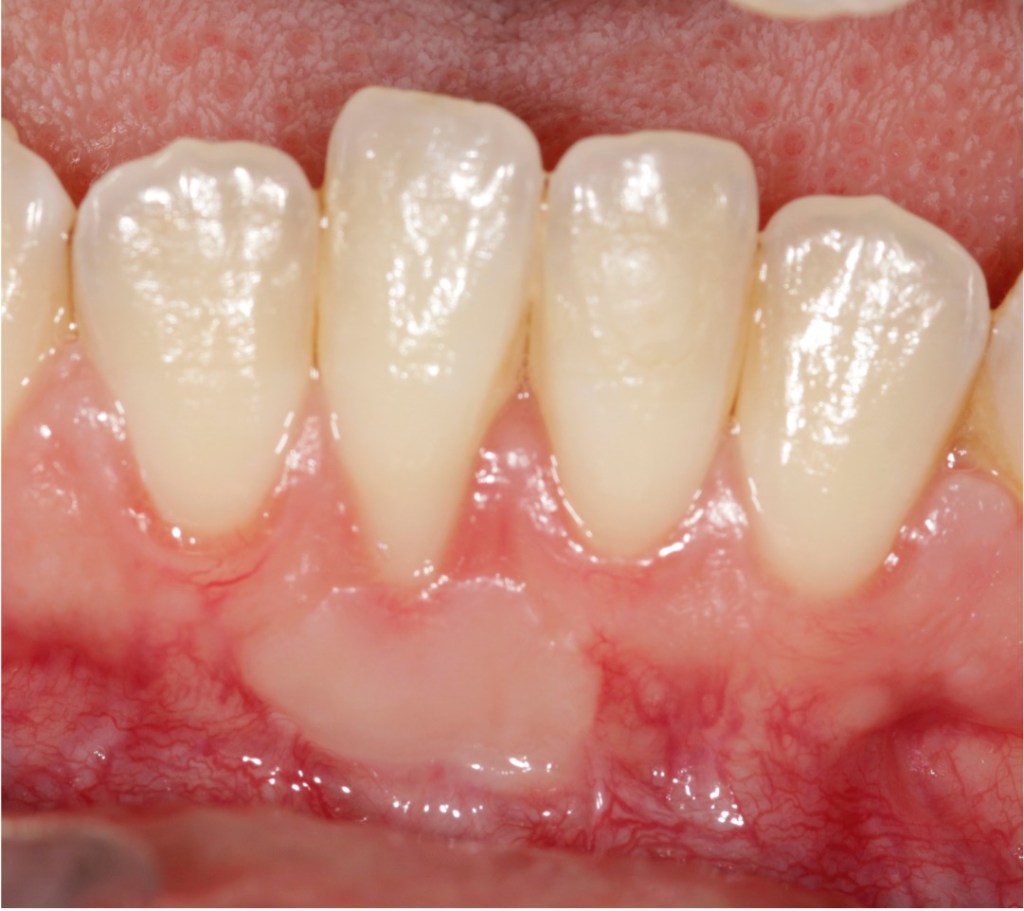

Recession surgery – connective tissue graft

A connective tissue graft is another way to cover recession. This takes a sub-layer of tissue from the palate. The advantage of this is more comfortable healing from the palate and a better colour match to the grafted area.